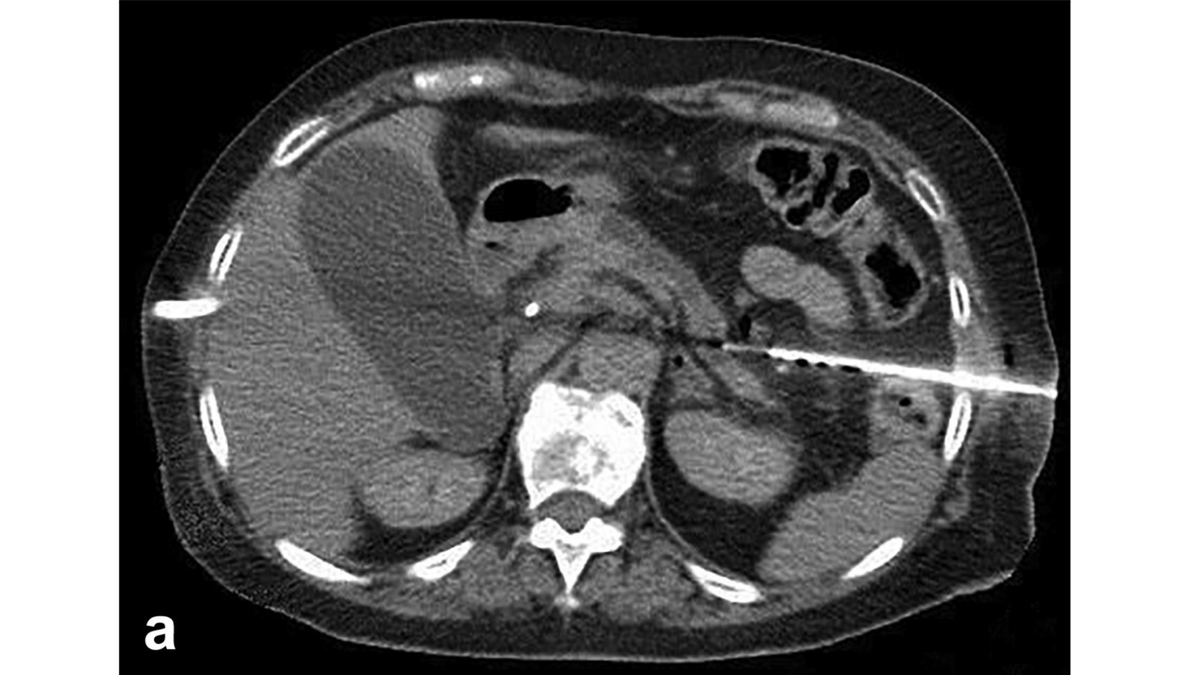

Prophylactic pre-pregnancy TAE decreased the growth and bleeding of renal AMLs during pregnancy.Dr.Othman Alshehri د.عثمان الشهري,Saudi Interventional Radiology Society,Society of Interventional Radiology,UT Houston_IR,PAIRS,Osman Ahmed,Ahmed Kamel MD, PhD, FSIR